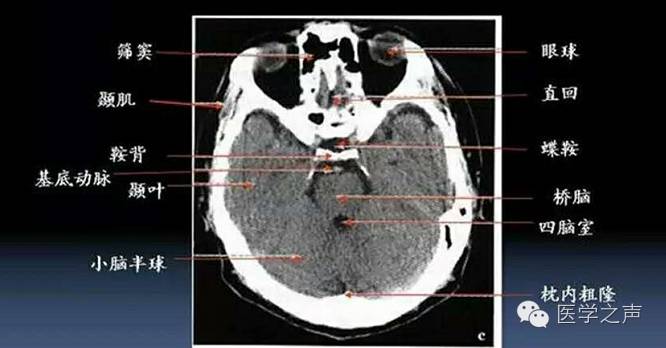

颞骨ct解剖及其常见病变